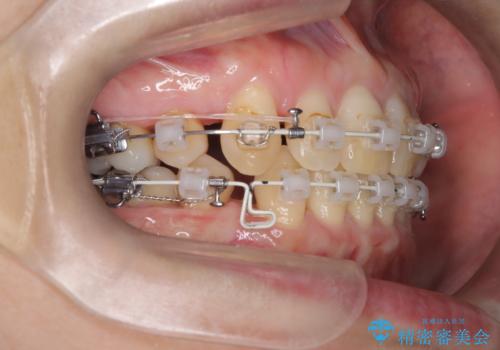

- 前歯の凸凹と前突感を改善するため、上下左右の4番を抜歯し、空いたスペースを利用して前歯を後方へ下げる審美ワイヤー矯正を計画しました。抜歯後は透明で目立ちにくい審美ブラケットを装着し、ワイヤーを用いて徐々に歯列を整えます。毎月1回の調整を通じて歯並びの変化を確認しながら、丁寧に矯正を進め、約2年で理想的な歯列と噛み合わせを完成させることを目指します。

前歯が前に出ていることや歯並びの凸凹が気になるという主訴でした。十分なスペースを確保するため上下左右の第一小臼歯(4番)を抜歯し、そこに前歯を移動させて整列を行いました。矯正装置には目立ちにくい透明なブラケットを選択し、見た目のストレスを軽減。矯正期間中は定期的な通院でワイヤーを微調整し、無理なく確実に歯を動かしました。治療後は前歯が自然な位置に下がり、口元の突出感が解消されるとともに、美しく整った口元に仕上がり、患者様にも大変喜んでいただけました。